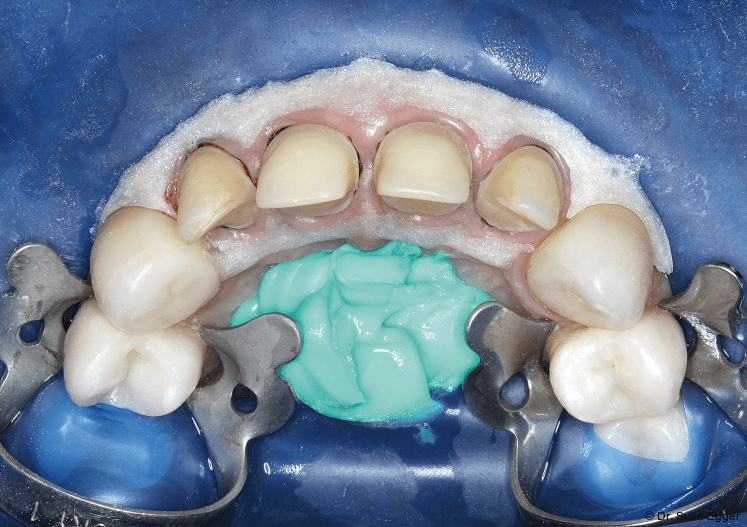

- Die Abdrucknahme erfolgt nach Entfernung des zuletzt gelegten Fadens (der zuerst gelegte Faden geringeren Durchmessers verbleibt im Sulkus) mittels eines A-Silikons in Doppelmischtechnik einzeitig: Umspritzung der präparierten Zähne mit dünnfließendem Material (Express Ultra-Light Body, 3M Espe) und Einbringen des schwerfließenden Materials, (Express Penta Putty, 3M Espe) in einen Abdrucklöffel (Rim Lock, DeTrey; Abb.13).

- Kieferrelationsbestimmung in habitueller Interkuspidation (HIKP) mit thermoplastischem Kunststoff (Bite Compound, GC).

- Gegenkieferabformung (UK) mit Alginat (Alginat, Cadco).